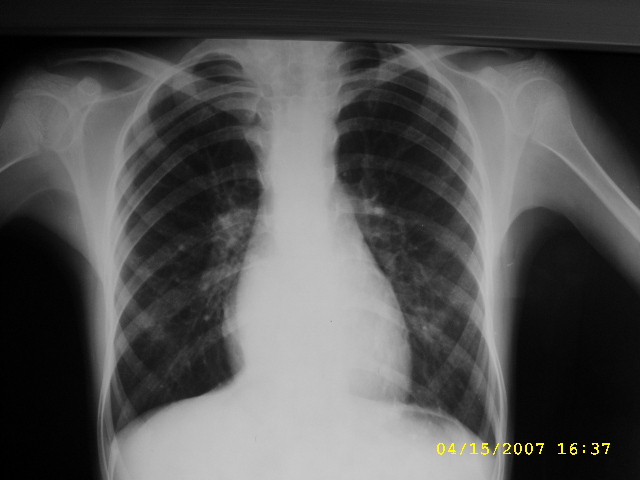

女,12,后纵隔占位十余年。